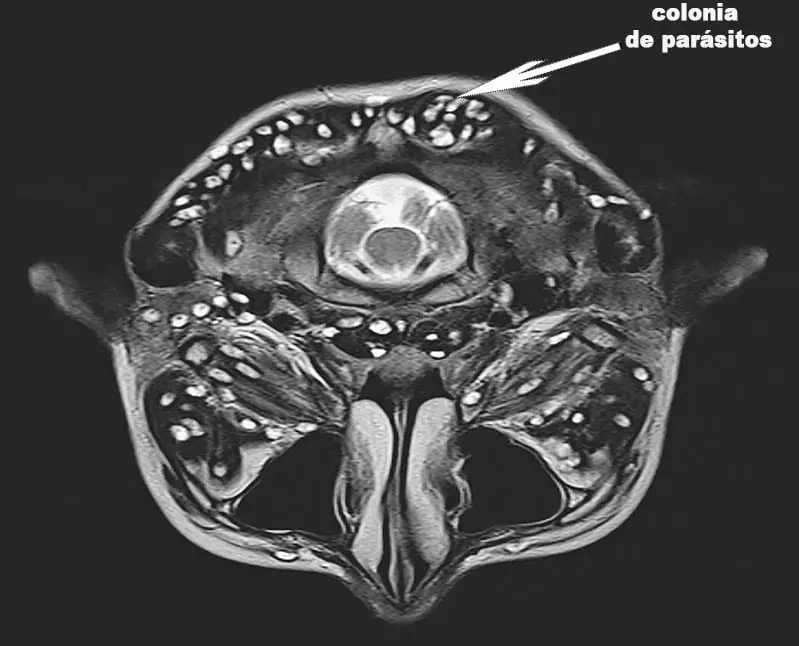

Si hay papilomas o verrugas en el cuerpo de una persona, entonces una colonia de parásitos mortales ya se ha establecido en los órganos internos y está devorando el tejido

2. Útero infectado por una colonia de parásitos. Desafortunadamente, ya era imposible deshacerse de ellos, porque los parásitos y sus larvas ya llenaron completamente el útero de este paciente y aumentaron su cantidad varias veces. Por lo tanto, era necesario quitarlo. La mujer fue rescatada. Sin embargo, la intoxicación del cuerpo fue tan severa que tuvo que someterse a un tratamiento especial después de la extracción del útero y, desafortunadamente, murió después de 3 años.